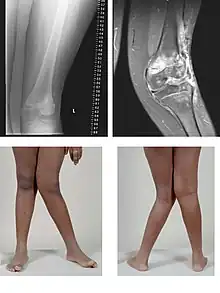

Valgus deformity of the knee (genu valgum), seen in MRI and photograph

• Knee: genu valgum (from Latin genu = knee) – the tibia is turned outward in relation to the femur, resulting in a knock-kneed appearance. Common causes of valgus knee (colloquially "knock-knee") in adults include arthritis of the knee and traumatic injuries.